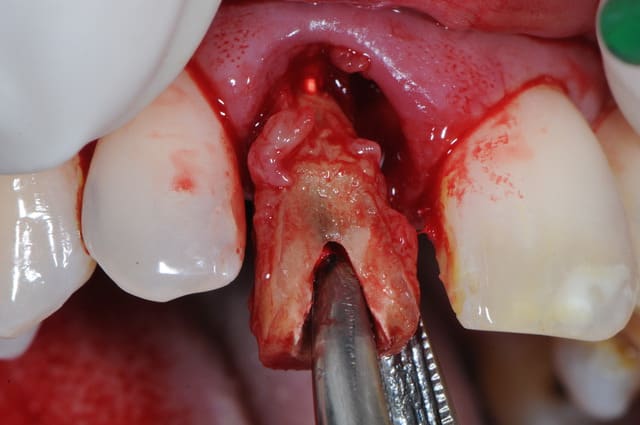

pas que pour le granulome...d'ailleurs...mais aussi parce que tu as une belle fracture vestibulaire qui fait que la corticale...bein y en a plus...ou quasi plus...

dans un cas comme çà, pour moi c'est extraction, curetage méticuleux, éponge hémostatique, une petite suture en haut pour bien tout stabiliser sans trop de tension et un petit bridge prov collé fait au composite, pourquoi pas "armé" avec une tresse résine (que tu trouves en petites bobines chez les vendeurs de maquettes...)

les 2 cas ne me semblent pas comparable dans la mesure ou tu as réussi à préserver un bandeau d'os vestibulaire presque au niveau des collets. Il permet un effet piquet de tente incomparable et évite les mauvaises surprises de perte importante de volume de biomat a la cicatrisation.

Dans l'autre cas la table vestibulaire est manquante, le résultat d'une EII beaucoup moins prévisible et dans un secteur esthétique j'aime pas jouer a la roulette russe.

Moi ce qui me choque , c est de greffer "en milieu infecté".